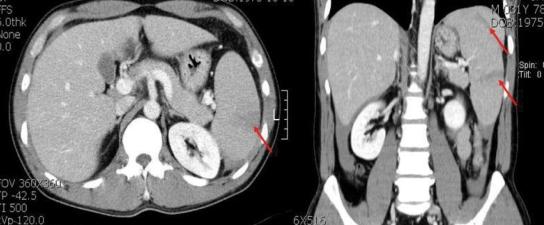

以病理性脾破裂为首发表现的急性髓系白血病 M2 一例。

A case of pathologic splenic rupture as the initial manifestation of acute myeloid leukemia M2.

A pathologic splenic rupture refers to a rupture without trauma. A splenic rupture as the initial manifestation of acute myeloid leukemia is extremely rare. In this study, we described a rare case of acute myeloid leukemia presenting principally as an acute abdomen due to a pathologic splenic rupture in a 35-year old male patient. We can assert that a pathologic splenic rupture in hematologic diseases is a potentially life-threatening complication, which necessitates immediate operative intervention. Any such patient complaining about left upper abdominal tenderness should be closely observed, and further diagnostic investigations (ultrasonograph of the abdomen, abdominal CT scan) should be initiated in order to rule out a splenic rupture. The oncologist should be aware of this rare initial presentation of acute myeloid leukemia (AML) M2, as the condition generally necessitates a prompt splenectomy.

摘要

病理性脾破裂是指无外伤的脾破裂。以脾破裂为首发表现的急性髓系白血病极为罕见。本研究描述了 1 例罕见的 35 岁男性病例,主要表现为急性腹痛,其原因为病理性脾破裂。我们可以断言,血液系统疾病中的病理性脾破裂是一种潜在的危及生命的并发症,需要立即进行手术干预。任何有左上腹压痛的此类患者都应密切观察,并进一步进行诊断性检查(腹部超声、腹部 CT 扫描)以排除脾破裂。肿瘤学家应该意识到这种急性髓系白血病(AML)M2 的罕见首发表现,因为这种情况通常需要迅速进行脾切除术。